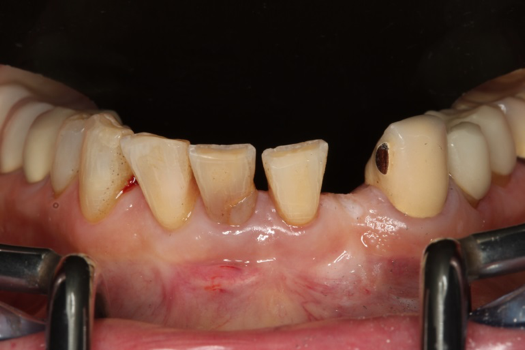

Fig 36. Anterior central view.

Figure 36

Fig 37. Pontic removal of No. 23 and teeth extractions.

Figure 37

Fig 38. Periodontal casualties.

Figure 38

The next case follows the digital protocol for fully guided surgery and prosthetics. A CBCT radiograph, digital impression, and digital photography were the cornerstones to the success of this case. The 3D data set was electronically delivered to the dental laboratory. The data were merged and the process to develop the plan was initiated. The use of CBCT was essential in this case, particularly due to minimal space for placement of individual implants and single-unit crowns. The patient's chief concern was that she wanted to have single-unit crowns instead of fixed crown-and-bridge restorations because she was worried that she would someday find herself in an assisted-living facility; if that were to happen, she wondered, who would help floss under her bridge work? Her decision was to have single implants with individual crowns. CBCT technology is much more accurate in evaluating space maintenance and management.10 Periapicals in the past were rather close for calculating spacing; however, the CBCT identifies the buccal-lingual dimensions as well as the mesial-distal measurements. On review of the completed proposals for implant placement and provisionals, it was determined that there was sufficient spacing for implant placement to allow appropriate emergence profiles for the provisionals and then eventually the final single-unit cemented crowns. The proposal was accepted, and a 3D-printed surgical stent was fabricated, along with the PMMA provisionals (Figure 29 through Figure 35).

On the day of surgery, the plan was to extract teeth Nos. 21, 23, 24, 25, and 26, place 3.0 x 13-mm implants in the anterior region due to limited spacing, and place a 4.1 x 10-mm implant in the No. 21 extraction site. Before the extractions were performed, the No. 23 pontic was sectioned from the existing 2-unit cantilevered bridge utilizing ceramic and metal high speed rotary cutting burs ZR 6881 and H34L (Komet-USA), respectively. After removal of the pontic and extractions, the surgical guide was verified to be seating positively (Figure 36 through Figure 38). Surgical guide protocol was followed, and all implants were successfully placed and torqued to a value of greater than 35 Ncm (Figure 39 and Figure 40). All implants were placed without flapping, with the exception of No. 23. The flap was elevated to reposition lingual keratinized tissue facially for enhanced esthetic tissue profile. The implants were then prepared with a high-speed carbide bur (Komet-USA) with copious amounts of water (Figure 41 and Figure 42). The one-piece 3.0-mm diameter implant served the needs of the patient's spacing requirements. Inter-occlusal space requirements and path of draw were verified. The PMMA provisionals were air abraded and relined with crown-and-bridge material (Figure 43 through Figure 45).